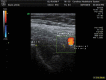

Objectives: Prudent dry needling techniques are commonly practiced with the intent to avoid large neurovascular structures, thereby minimizing potential excessive bleeding and neural injury. Patient position is one factor thought to affect the size of the safe zone during dry needling of some muscles. This study aimed to compare the size of the needle safe zone of the iliacus muscle during two different patient positions using ultrasound imaging. Methods: The distance from the anterior inferior iliac spine (AIIS) to the posterior pole of the femoral nerve was measured in 25 healthy participants (11 male, 14 female, mean age = 40) in both supine and sidelying positions using a Chison Eco1 musculoskeletal ultrasound unit. The average distance was calculated for each position and a two-tailed, paired t-test (α < 0.05) was used to examine the difference between positions. Results: The mean distance from the AIIS to the posterior pole of the femoral nerve was statistically greater with participants in the sidelying position (mean[SD] = 35.7 [6.2] mm) than in the supine position (mean[SD] = 32.1 [7.3] mm, p < .001). Discussion: Although more study is needed, these results suggest that patient positioning is one of several potential variables that should be considered in the optimization of patient safety/relative risk when performing trigger point dry needling. Level of Evidence: Level 4 (Pre-Post Test).